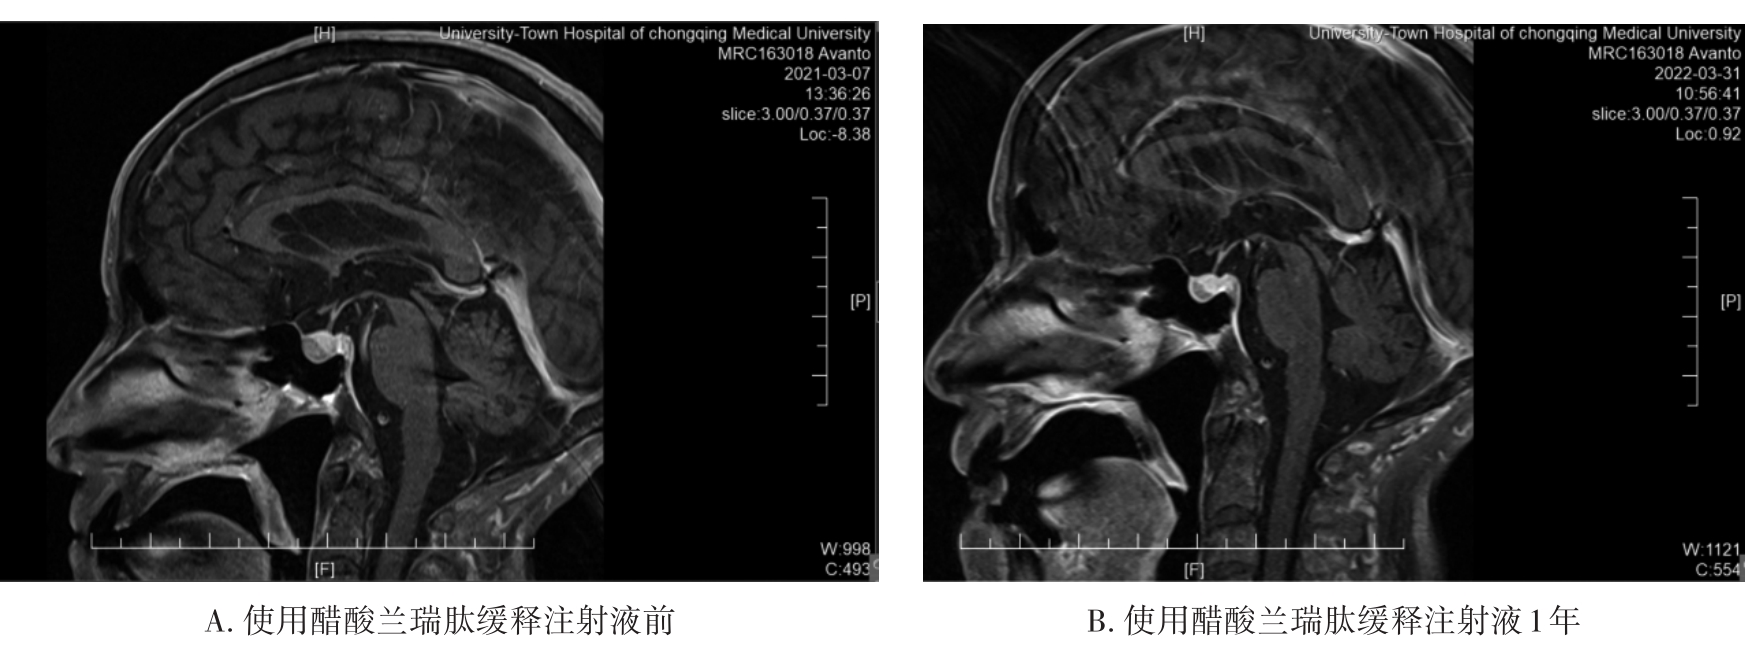

• 长效生长抑素类似物治疗垂体促甲状腺激素腺瘤1例并文献复习

2023, 48(9):1116-1121. DOI: 10.13406/j.cnki.cyxb.003336

摘要 (120) HTML (37) PDF 677.52 K (209) 评论 (0) 收藏

摘要:

• 0+1

• 1+1

• 2+1